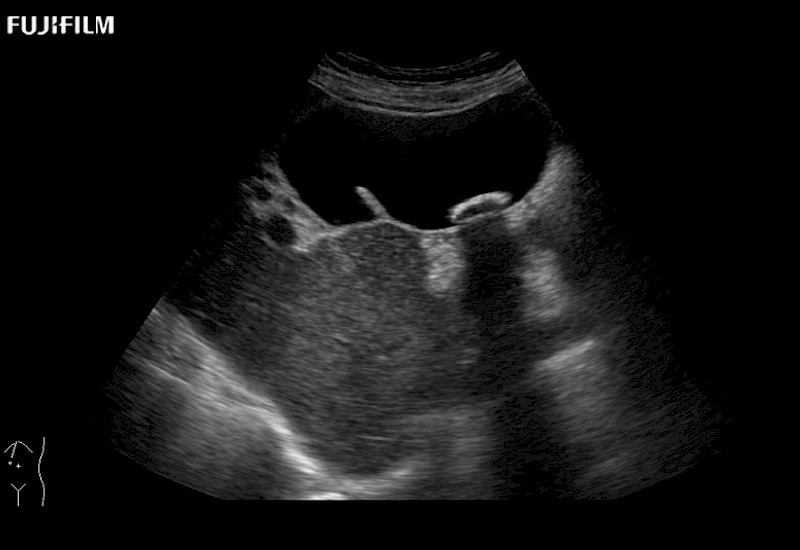

Exclusive linear array robotic surgery transducer.

Robot-Assisted Partial Nephrectomy Brochure (.pdf)

Features:

Main Specifications: